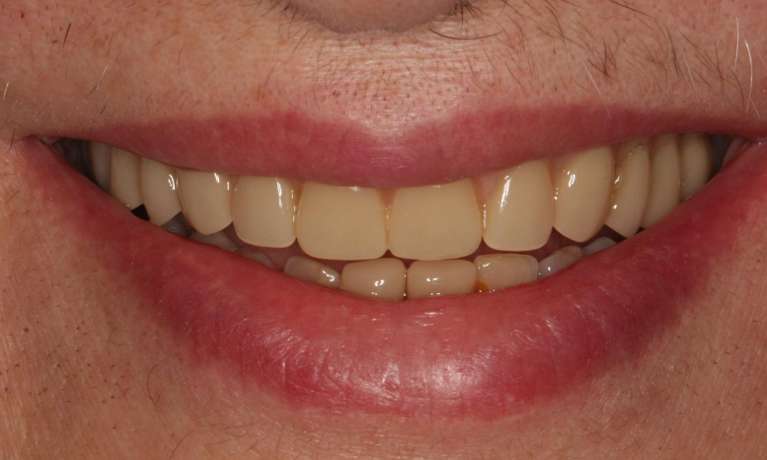

A young teenage with gaps, missing teeth and heavily decayed teeth came to our practice. The whole procedure started with restoring his teeth, 2 years of braces, and and then finally crowns in his early 20s to create the finished smile. His new smile will be maintained with regular dental cleanings and maintenance.